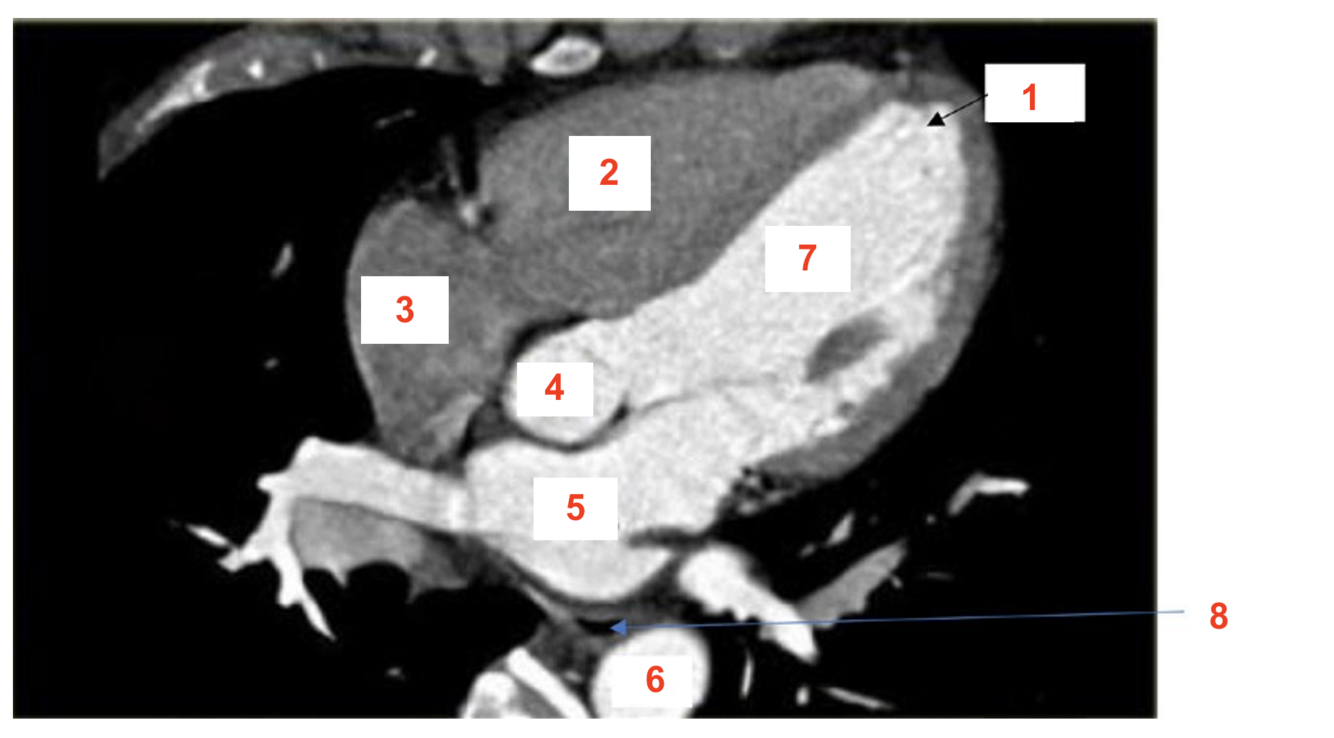

Q

label

A

1. SA node

2. Inter-atrial pathways (bachmans bundle)

3. Internodal pathways

4. AV node

5. Bundle of HIS

6. RIGHT bundle branch

7. LEFT bundle branch

8. Purkinje fibres